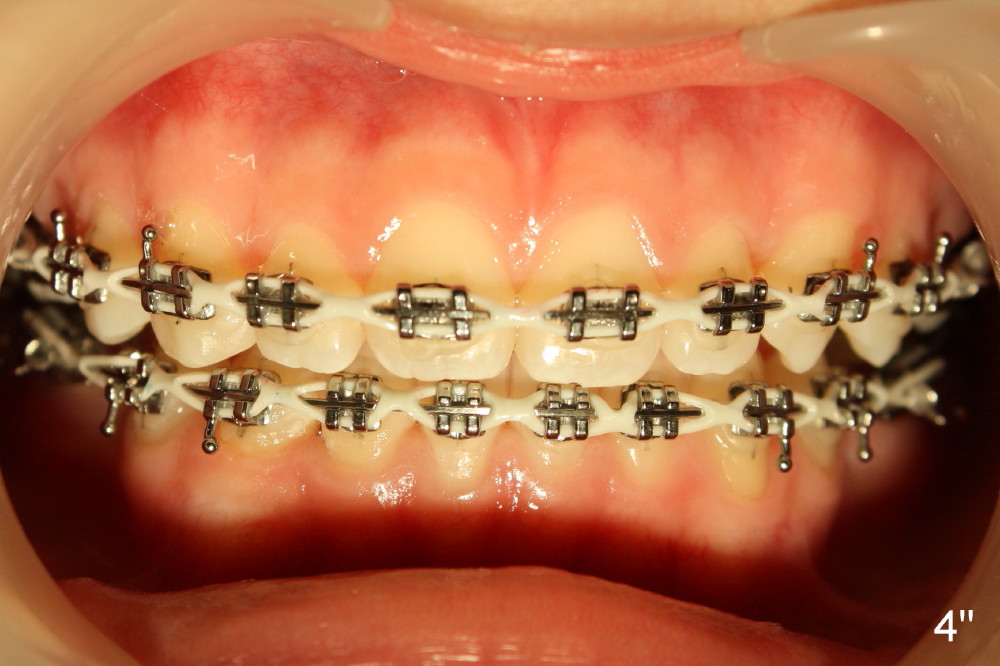

A 13-year-old Asian girl seeks orthodontic treatment for crowding. The lower 2nd bicuspids are congenitally missing (Fig.1,8), whereas the upper right one rotates 180° and the upper left is partially impacted (Fig. 1, 7). The lip muscles strain when the lips close (Fig.3). Orthodontic treatment started with extraction of four affected teeth (#4,13, K and T) 6 months ago. .018' niti wires are being used. Dental midlines do not coincide preop and intraop (Fig.4,4'). Pre-op front view shows that the upper dental midline coincides with the facial one (Fig.1'). There is Class I canine and molar relationship on the right (Fig.5,5',9,9'); open bite on the left (Fig.6,6',10,10').

Update: The left open bite was closed less than one month by wearing elastics between upper and lower teeth (Fig. 6'''). The occlusal plane and midline improve (Fig.4''). Wires have gradually changed to .016x.016, .016x.022 and now .018x.025 with power chains. All the spaces are closed except the one in LR (Fig.7''-10''). What I cannot accomplish is to fix meisal (Fig.5'' (white line), 9'') and lingual (Fig.8'' arrows) inclination of LR molars, although elastic is instructed to be placed between UR7 buccal and LR7 lingual. The rectangular wires could be twisted to fix lingual inclination. Which should be done first: LR space or LR molar inclination? Click each figure for magnification.